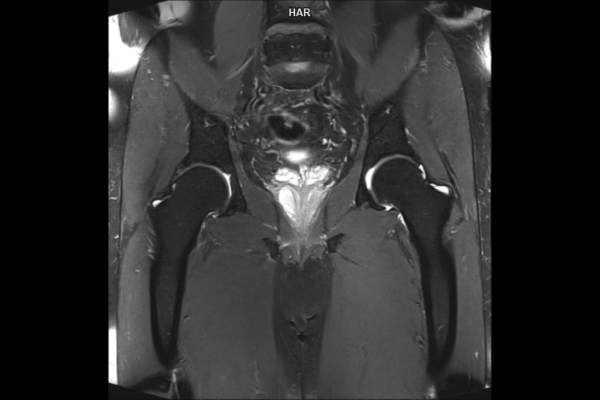

Detailbild MRT

• Bildgebende Endometriose-Abklärung

Wir bieten ein breites Spektrum an Untersuchungen an, von Standarduntersuchungen der Gelenke, Organe oder großflächigen Körperregionen bis zu Spezialuntersuchungen zum Beispiel des Herzen oder der Gefäße. Zusätzlich werden Angiographien (Darstellung von Blutgefäßen), Endometriose-Abklärungen und Mamma-Untersuchungen durchgeführt. Genauere Details können Sie der MRT/CT-Übersicht und der Preisliste entnehmen, oder Sie wenden sich direkt an unser Team, das Sie gerne zur passenden Untersuchung berät.

Ja, unsere Radiologie bietet auch Sonographie- (Ultraschall-)Untersuchungen an. Untersucht werden unter anderem Abdomen, Becken, Leiste, Brust, Venen und Gefäßen.